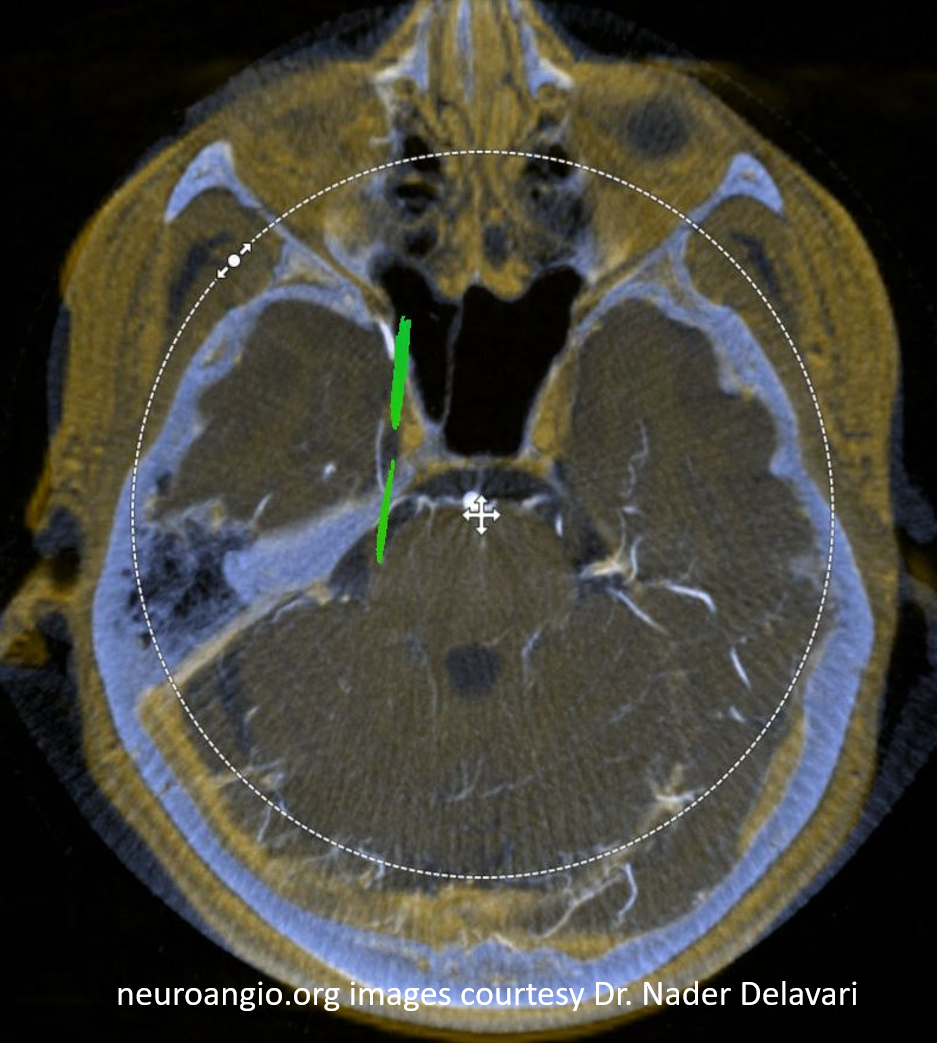

And, in case you really dont believe its the trigeminal artery, check out these co-registration images of angio (axial MIP reconstructions of rotational angio) and finally with superimposed tractography of the Vth nerve! Images courtesy Dr. Nader Delavari

Superimposed MRI and angio axials (our trigeminal artery is shown bi arrow)

Now with tractography of CN V